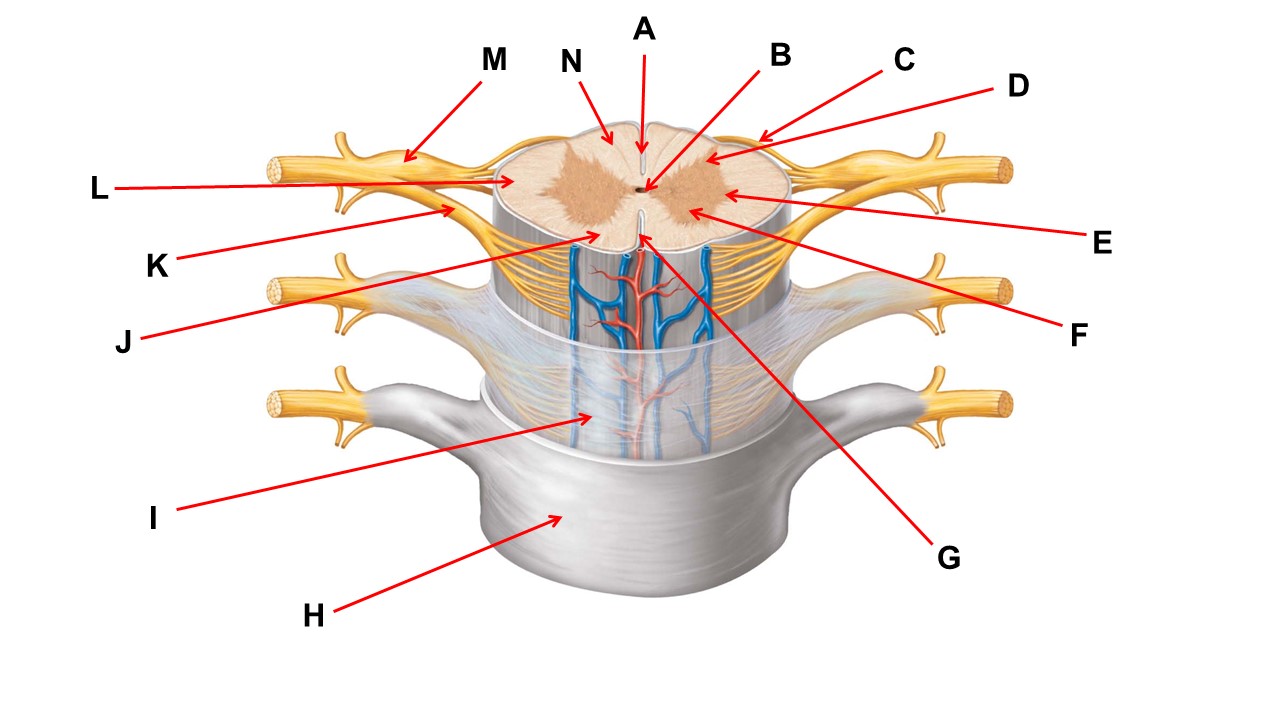

Name the region within bracket D.

Name the region of tissue surrounding the tip of arrow E.

Name the region of tissue surrounding the tip of arrow B.

dorsal horn

Name the structure at the tip of arrow K.

ventral root

Name the region of tissue surrounding the tip of arrow J.

ventral column

Name the region of tissue surrounding the tip of arrow E.

lateral horn

Name the region of tissue surrounding the tip of arrow N.

dorsal column

Name the deep groove at the tip of arrow G.

anterior median fissure

Which structure(s ) would be found in the area at the tip of arrow D.

cell bodies of interneurons

Name the region of tissue surrounding the tip of arrow E.

ventral horn

Name the region within bracket G.

gray commisure